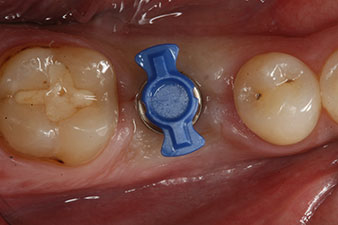

Fig. 1: Initial clinical situation after healing of extraction alveolus 36: The bone base is wide and there is sufficient keratinized gingiva.

A 28-year-old patient with a history of heavy smoking had to have tooth 36 extracted as a result of recurring apical periodontitis.

Due to the generally intact neighbouring teeth the only way to fill the gap was an implant.